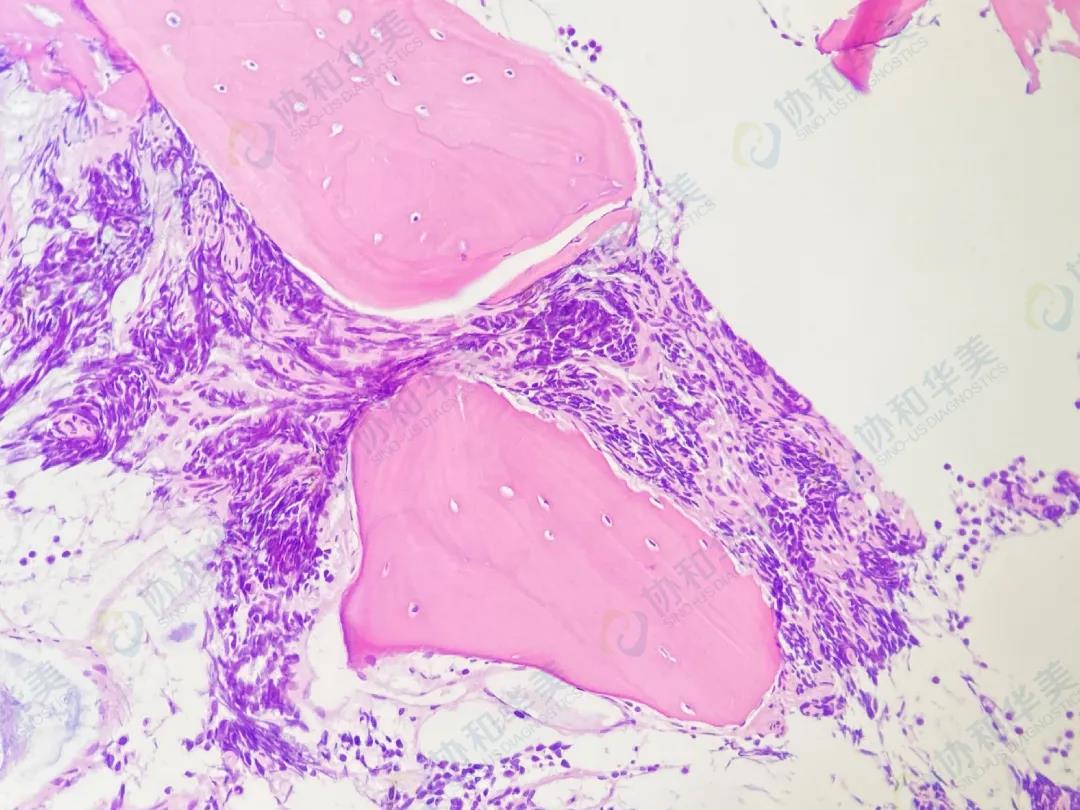

病理切片

HE染色                                                 HE染色

【诊断结果】

横纹肌肉瘤侵犯骨髓